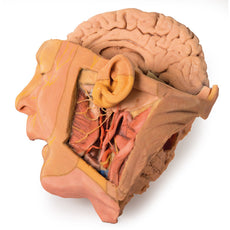

3D Printed Brain Hemisection

This 3D model is a midsagittal hemisection through a whole brain, preserving the right side anatomy and deep brain

structures and spaces visible in the midline. In lateral view, the right cerebral and cerebellar hemispheres are

covered in the arachnoid mater. In the midline view, the brain regions from the cerebrum to the medulla oblongata

are preserved. Centrally, the third ventricle is opened, with an intact septum pellucidum superiorly positioned and

obscuring the lateral ventricles within the cerebral hemisphere. On the inferior margin of the third ventricle both

the right mamillary body and right optic tract can be observed, whereas posteriorly the cerebral aqueduct can be

observed extending across the midbrain between the tectum and tegmentum towards the fourth ventricle (between the

cerebellum and pons). The cerebellum is separated from the occipital lobe by a preserved portion of the tentorium

cerebelli, and in cross-section the cerebellar cortex helps form the prominent arbor vitae.

A series of arterial

branches have been false coloured to contrast their course across the preserved brain structures. In the midsagittal

view the anterior cerebral artery courses from around the corpus callosum to supply the cingulate gyrus and other

midline cortical regions. The base of the middle cerebral artery can be seen passing deep between the temporal and

frontal lobes, with the posterior communicating artery connecting it to a small remnant of the posterior cerebral

artery. Adjacent to the posterior cerebral is the superior cerebellar artery, extending laterally to pass between

the temporal lobe and the cerebellum before passing deep into the transverse fissure.